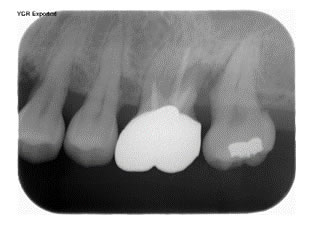

症例1

治療の特徴(患者T様)

平成13年7月7日 右下第一大臼歯頬側に膿瘍形成 著しい腫れ形成 著しい腫れ

- 男性33歳

- 平成14年11月9日 どうしても抜きたくないということで歯周外科処置する。

- その後H16から1~2カ月おきにメインテナンス。

- 平成16年6月11日 歯周治療により骨が出来てきています。

口の中から細菌を除去し、良好な環境を維持していくことによって歯周組織である歯槽骨や歯肉、歯根膜は生き生きとよみがえってきます。継続は力なりと申しますが根気良く治療を続けることで健康が回復し維持されます。

| 歯周外科に対するデメリット | 外科処置ですので麻酔が必要な処置である。全身疾患がある場合には先に体調管理を行う必要がある。処置後1週間ぐらいは治療部位のブラッシングが出来ない。冷たいものがしみることがある。 |

|---|---|

| 治療期間 | 4年7カ月 |